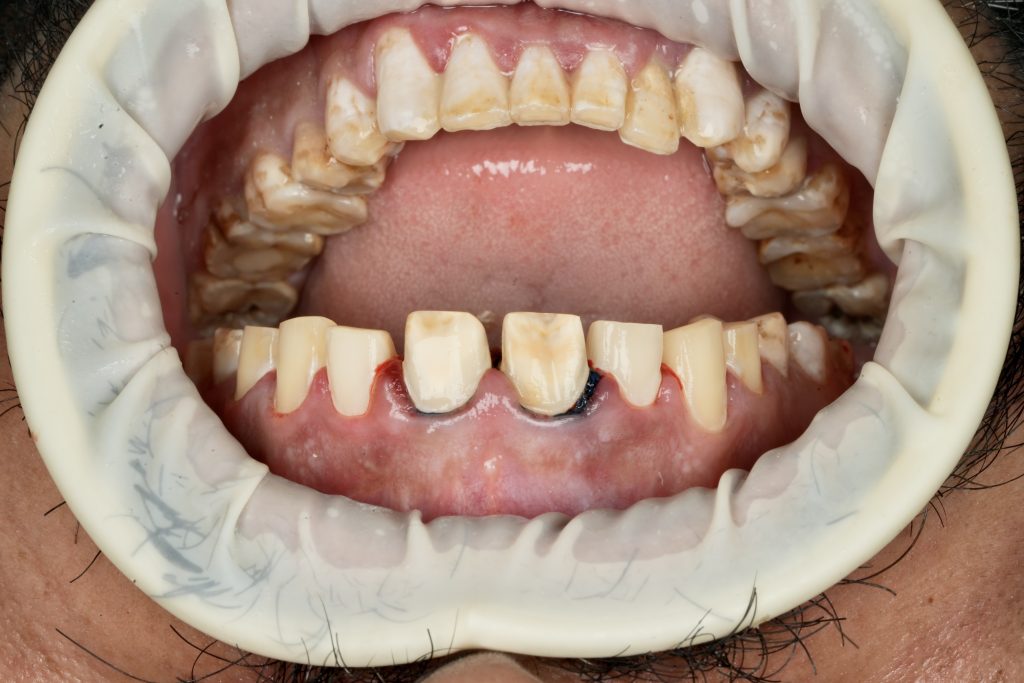

The patient sought esthetic improvement for uneven incisal edges, discolored anterior teeth, and disproportionate gingival display (Fig 1). A digital smile simulation and mock-up try-in were performed to assess tooth proportion, midline alignment, and incisal curvature. The plan prioritized enamel conservation and optical harmony.

Each veneer was etched with 9 % HF acid for 20 seconds, silanated, and dried. Teeth were treated with 37 % phosphoric acid and universal adhesive (Clearfil Universal Bond Quick). Light-cure resin cement (Variolink Esthetic LC) was applied under full-arch rubber-dam isolation. Excess cement was removed and polymerization performed for 40 s per surface (Fig 4).